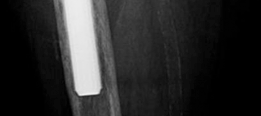

History of presenting complaint : Presents with a draining wound and well-fixed cementless components with a constrained liner due to absent abductor mechanism (Fig. 19.12). Treated with Prostalac and six weeks of IV antibiotics (Fig. 19.13). At the 6-week point, the patient sustained a ground level fall with an acetabular fracture and displacement of the acetabular Prostalac (Fig. 19.14).

Diagnosis : Treated MRSA infection of the right THA with acute acetabular fracture and patient now unable to mobilize due to pain (Fig. 19.14).